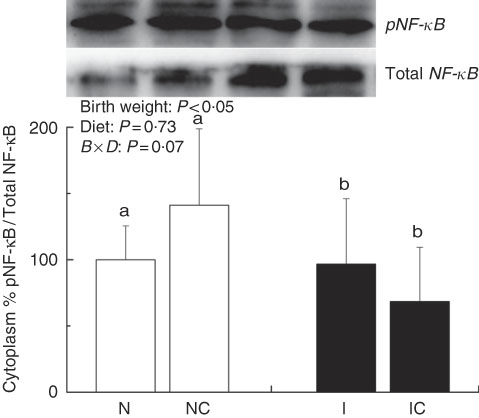

The IUGR rats exhibited higher (P<0·05) phosphorylated IκBα (Fig. 6) and nuclear phosphorylated NF-κB (Fig. 7) levels and lower (P<0·05) cytoplasmic phosphorylated NF-κB (Fig. 8) levels in the liver than in the NBW rats. In addition, the phosphorylated levels of JAK2 (Fig. 9) and STAT3 (Fig. 10) were higher (P=0·24, P=0·01) in the IUGR rats than in the NBW and NC groups. Dietary curcumin supplementation decreased the phosphorylated levels of IκBα (P<0·05) and JAK2 (P>0·05), and NF-κB (P>0·05) in the nucleus and cytoplasm of liver in the IC group.

Fig. 8 Abundance of phosphorylated NF-κB in the cytoplasm of normal birth weight (![]() ) rats (N), normal birth weight rats supplemented with curcumin (NC), intra-uterine growth retardation (IUGR,

) rats (N), normal birth weight rats supplemented with curcumin (NC), intra-uterine growth retardation (IUGR, ![]() ) rats (I) and IUGR rats supplemented with curcumin (IC) (12 weeks of age). B, birth weight; D, diet; B×D, interaction between the corresponding parameters. Results were corrected for nuclear protein, n 6/group. a,b Mean values with unlike letters were significantly different when a significant interaction was observed (P<0·05).

) rats (I) and IUGR rats supplemented with curcumin (IC) (12 weeks of age). B, birth weight; D, diet; B×D, interaction between the corresponding parameters. Results were corrected for nuclear protein, n 6/group. a,b Mean values with unlike letters were significantly different when a significant interaction was observed (P<0·05).

IUGR neonates are associated with a high risk of inflammation and oxidative stress( Reference Tarryadkins, Fernandeztwinn and Hargreaves 28 ). TNF-α is a key immune modulator, which can activate chemotactic cytokines and produce free radicals, leading to oxidative stress( Reference Starke, Daniel and Dumont 32 ). Furthermore, TNF-α, IL-1β and IL-6 have been implicated as prototype pro-inflammatory cytokines in the pathogenesis of sepsis( Reference Deventer 33 ). Higher TNF-α, IL-1β and IL-6 levels were observed in the serum of IUGR rats, which implied that pro-inflammation occurred in the body. Reports had demonstrated that a strong pro-inflammatory bias existed in IUGR with placental insufficiency( Reference Raghupathy, Al-Azemi and Azizieh 8 ). Significantly high concentrations of TNF-α, IL-1β and IL-6 in IUGR rats were significantly decreased after dietary curcumin supplementation, suggesting that curcumin could reduce inflammatory responses in the serum. These results are similar to those of previous studies in cells( Reference Liu, Shang and Li 34 ) and rats( Reference Soetikno, Sari and Veeraveedu 35 ). The liver is an important organ, and liver dysfunction has been observed in IUGR newborn pigs( Reference Junjun, Lixiang and Defa 7 ). The activities of AST and ALT are positively correlated with portal flow( Reference Kuo, Li and Alfrey 36 ). Hepatic ALT is usually located in the cytoplasm, whereas AST is distributed in the cytoplasm and mitochondrial fractions. However, when the structure of the liver is seriously damaged, ALT and AST are released into the circulatory system, resulting in the improvement of ALT and AST activity in the serum( Reference Nyblom, Berggren and Balldin 37 ). In this study, the activities of serum AST and ALT in the IUGR group were higher than those in the NBW group. The increased activities of serum ALT and AST are generally accepted biomarkers for hepatic dysfunction( Reference Tang, Chao and Xing 38 ). The vacuolisation and cell oedema from the histological examination of liver sections were prevalent in hepatocytes of IUGR rats, which revealed histological damage in the liver of IUGR rats. Meanwhile, fat cells also had mild denaturation. Similar to our findings, IUGR fetuses had a higher activity of glutamate oxaloacetate transaminase and impaired liver function than the normal ones( Reference Liu, Lin and Wang 39 ). After curcumin supplementation, the abnormal levels of serum AST and ALT and liver histological damage improved, and these results were not different from those observed in the normal condition. Previous studies had shown that curcumin could significantly reduce the levels of serum AST and ALT( Reference Zhao, Song and Chai 40 ) and liver injury in mice( Reference Zhang, Xu and Zhang 16 ) and rats( Reference Toydemir, Kanter and Erboga 22 ). Our findings indicated that diets supplemented with curcumin attenuated liver injury and inflammation in IUGR rats. Thus, we concluded that the protective effects of curcumin on the liver may be very important in IUGR rats. To investigate the immunomodulatory mechanisms of curcumin, we detected the expressions of the NF-κB and JAK/STAT pathways in the liver. NF-κB is found in cytoplasm bound to IκB. In response to various stimuli, including cytokines, stress and bacterial pathogens, the latent cytoplasmic NF-κB/IκB complex is activated by phosphorylation( Reference Hiscott, Kwon and Genin 41 ). Phosphorylation of IκB induces their ubiquitination, proteosome degradation and, subsequently, NF-κB release and nucleus translocation( Reference Echeverri, Nancy and Mockus 42 ). NF-κB is one of the most ubiquitous eukaryotic transcription factors that regulate the expression of genes associated with control of inflammatory responses, cellular proliferation/growth, cell adhesion and other processes( Reference Chen, Castranova and Shi 43 ). Our results showed that IUGR induced increased levels of phosphorylated IκBα and nuclear NF-κB and decreased levels of cytoplasmic phosphorylated NF-κB in the liver. Similar to our study, Zhong et al.( Reference Zhong, Li and Huang 44 ) also reported that the IκB was activated and the expression of NF-κB was increased by IUGR. These results suggested that the activation of the NF-κB/IκB complex might be related to increased levels of cytokines in IUGR, including TNF-α and IL-1β. The JAK2/STAT3 pathway is known to be involved in the immune response of numerous cytokines, including IL-6, and activated in response to injury( Reference Yang, He and Hao 45 ). Our results demonstrated that IUGR induced high levels of phosphorylated JAK2 and STAT3 in the liver. The activation of the JAK/STAT3 pathway might be the result of increased IL-6 in IUGR rats. Our results also showed that expression levels of Tnfa, Il1b and Il6 were up-regulated in the liver of IUGR rats. Importantly, dietary curcumin supplementation obviously inhibited the phosphorylation levels of the NF-κB pathway and JAK2 in IUGR rats and down-regulated the expression of those downstream genes. These observations supported that curcumin attenuated inflammation through the NF-κB( Reference Soetikno, Sari and Veeraveedu 35 , Reference Surh, Chun and Cha 46 ) and JAK/STAT pathways( Reference Kim, Park and Joe 47 ) in the liver of IUGR rats, which resulted in the negative regulation of cytokines (TNF-α) and pro-inflammatory interleukins (IL-1β and IL-6)( Reference Reyes-Gordillo, Segovia and Shibayama 48 ).